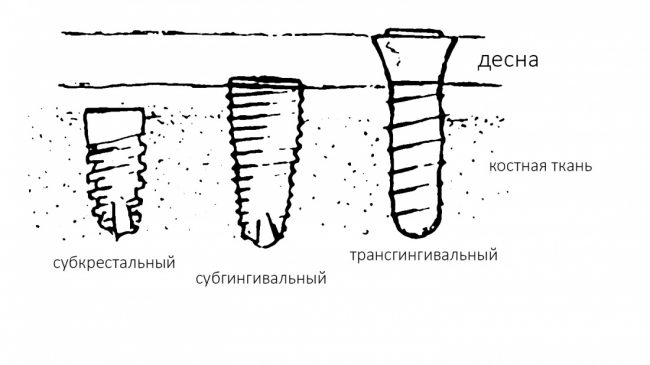

Помнится, в части, посвященной дизайну и конструктиву, мы рассмотрели три существующих типа имплантатов:

И, разумеется, если речь идёт о позиционировании по глубине погружения, то для разных типов имплантатов оно будет проводиться по-разному.

Субкрестальные имплантаты (Ankylos, Bicon и т. д.): глубина погружения ограничена размером эндооссальной части супраструктур. В частности, для Ankylos (Dentsply Sirona Implants) она составляет 4.5 мм, и это значит, что погружение имплантата на большую глубину создаст проблемы с его протезированием.

Трансгингивальные имплантаты (XiVE TG, Straumann TL, Zimmer Spline и т. п.). имеют выраженную трангингивальную часть в виде полированной шейки (см. часть III про дизайн имплантов). Предполагается, что она будет находиться выше уровня костной ткани:

собственно, поэтому и называется трансгингивальной.

Следовательно, имплантат погружается на такую глубину, чтобы его полированная часть всегда оставалась выше уровня костной ткани. Не рекомендуется, не нужно, да и просто нельзя погружать трангингивальный имплантат в костную ткань до уровня ортопедической платформы! Это, кстати, одна из самых распространенных ошибок на имплантах Zimmer Spline и Straumann Standart (TL). Почему? потому, что хирургический протокол не предполагает подготовку лунки под расширяющуюся трансгингивальную часть, в результате она создает избыточное давление на окружающую кортикальную кость, а это, как говорится, превед, периимплантит. И примеров тому масса.

Вообще, давайте возьмём за правило:

любая полированная часть любого имплантата должна оставаться выше уровня костной ткани.

Это относится ко всем имплантам, включая субгингивальные. Кстати, поговорим о них.

Учитывая то, что на сегодняшний день субгингивальные импланты составляют более 90% рынка, их позиционированию по глубине следует уделить больше внимания.

Итак, существенным отличием (и признаком) субгингивальности является полированный торец (как у Nobel Biocare) или полированная фаска (Astratech Osseospeed, XiVE S, Dentium и пр.) по периметру ортопедической платформы: